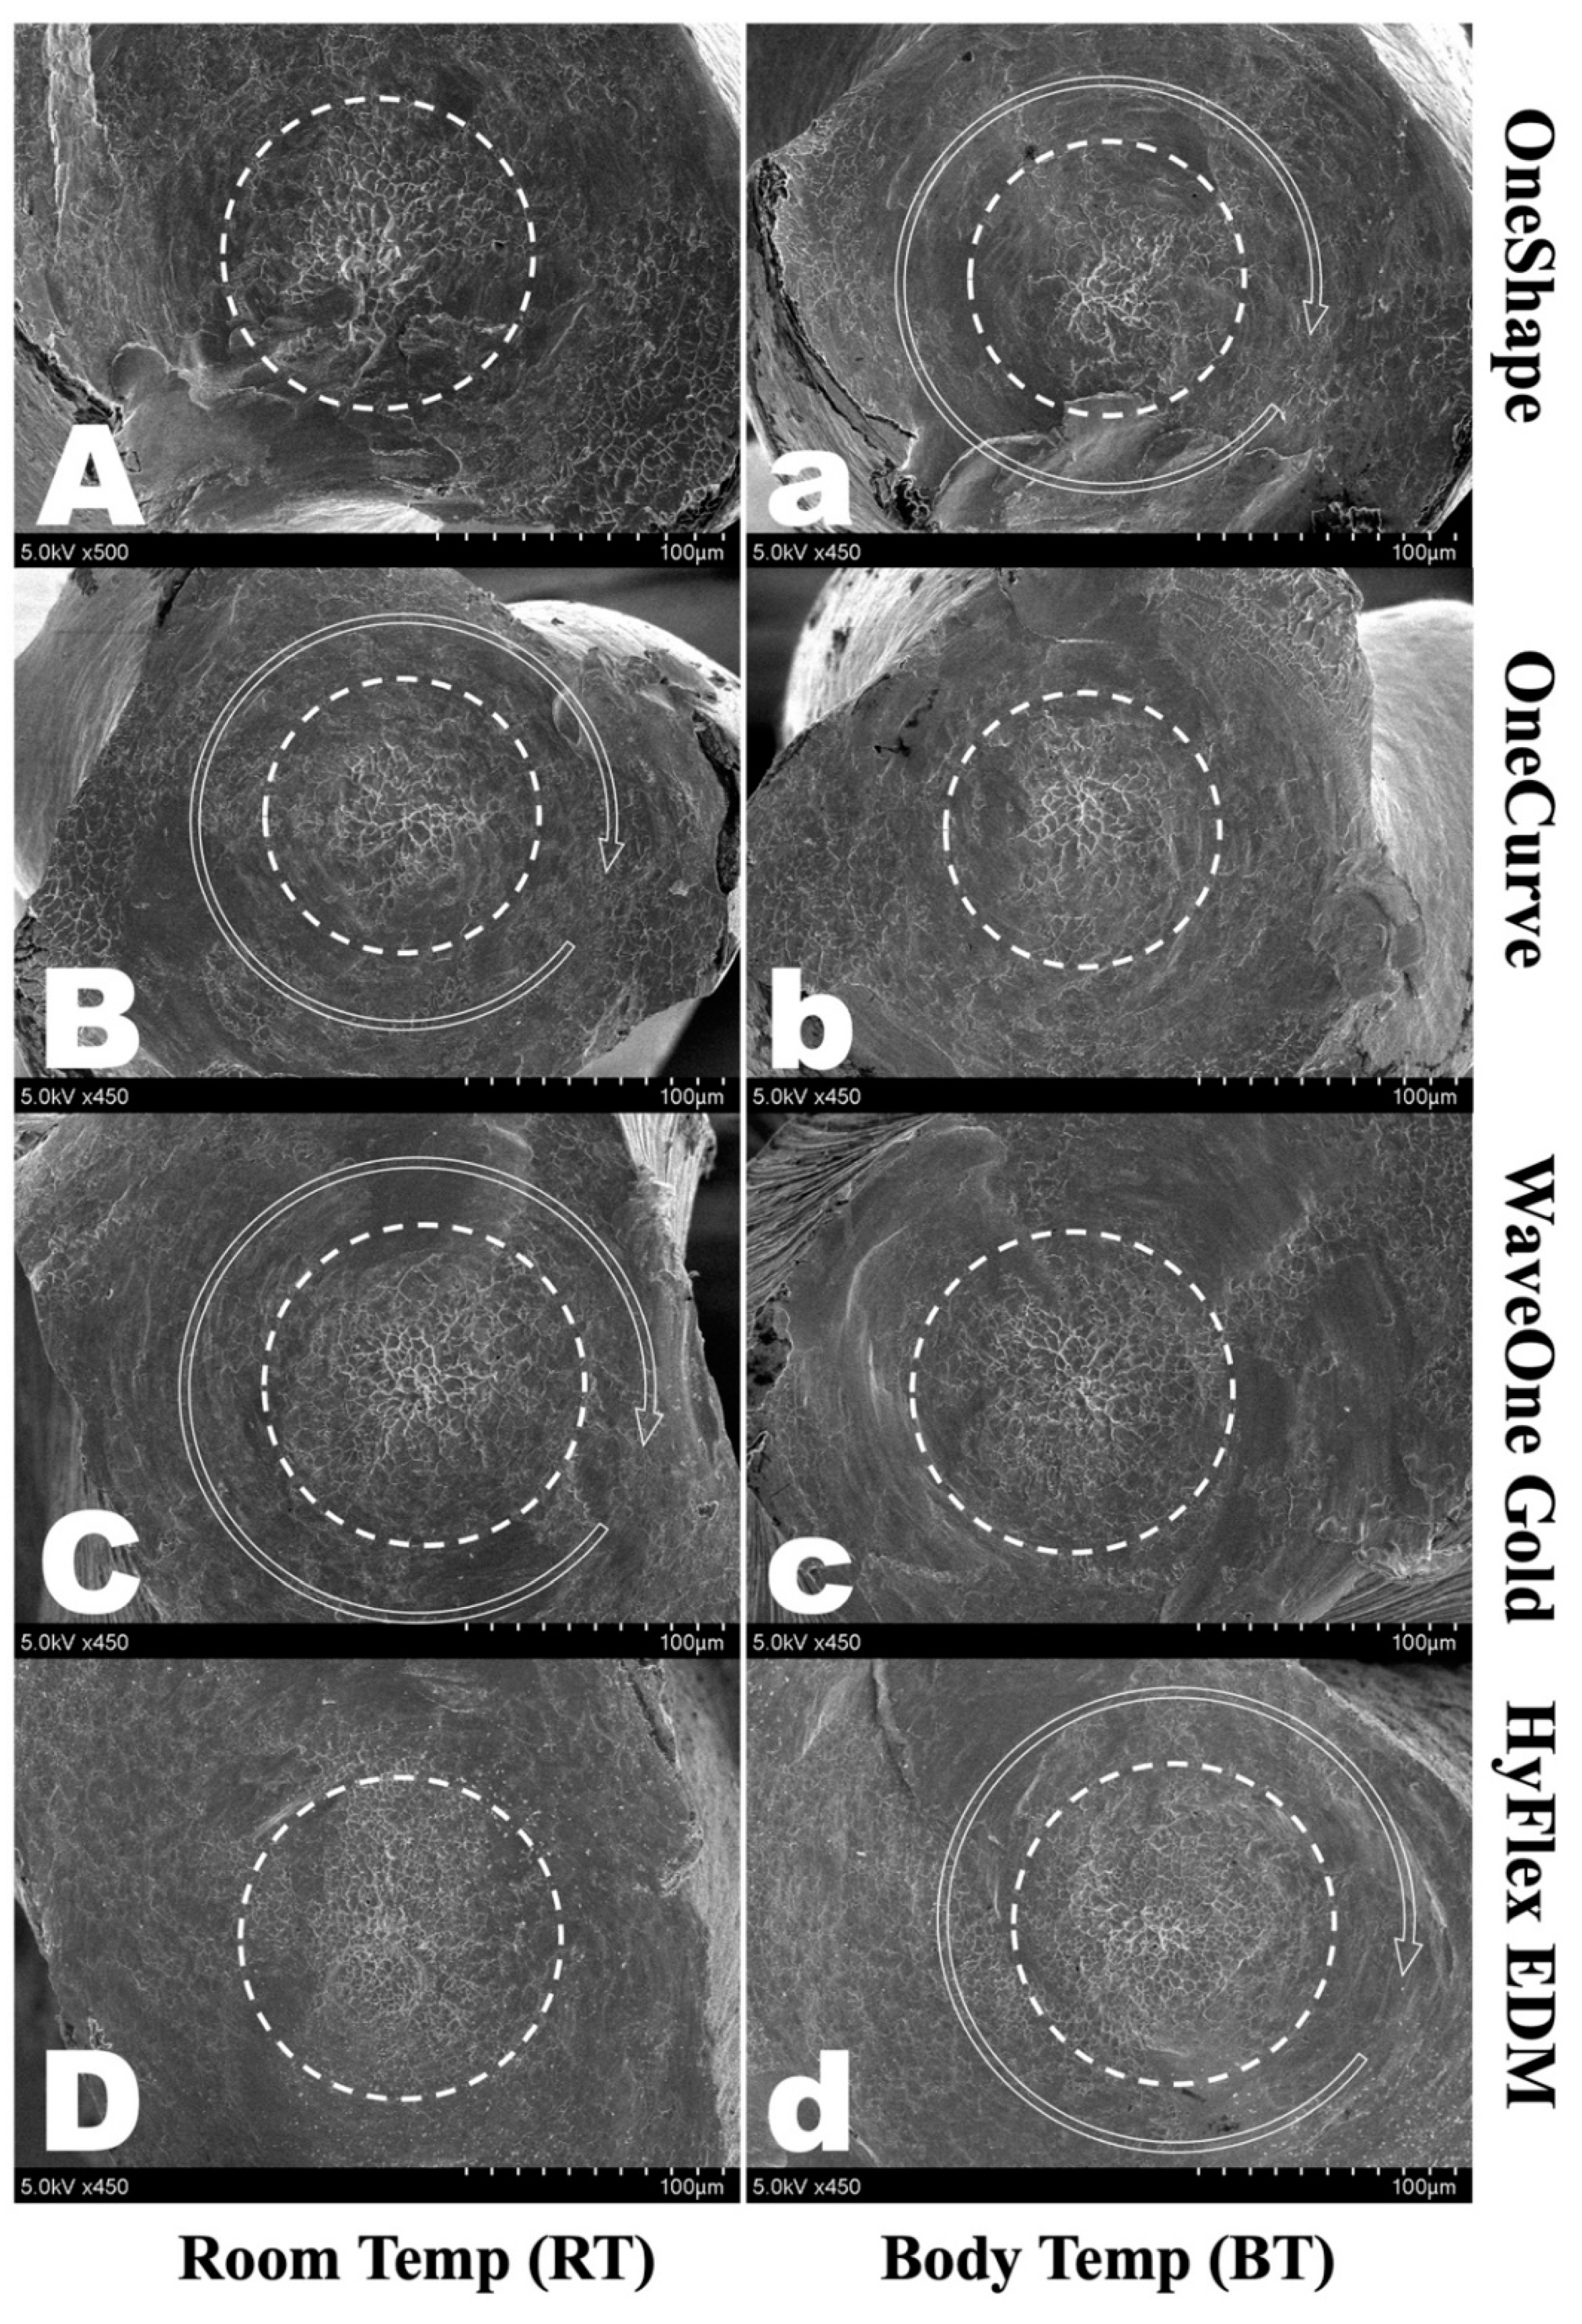

3.3. Scanning Electronic Microscopic Analysis

- Alapati, S.B.; Brantley, W.A.; Svec, T.A.; Powers, J.M.; Nusstein, J.M.; Daehn, G.S. SEM observations of nickel-titanium rotary endodontic instruments that fractured during clinical Use. J. Endod. 2005, 31, 40–43. [Google Scholar] [CrossRef]

- Alexandrou, G.B.; Chrissafis, K.; Vasiliadis, L.P.; Pavlidou, E.; Polychroniadis, E.K. SEM observations and differential scanning calorimetric studies of new and sterilized nickel-titanium rotary endodontic instruments. J. Endod. 2006, 32, 675–679. [Google Scholar] [CrossRef] [PubMed]